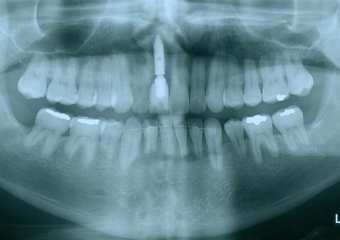

Raio X final